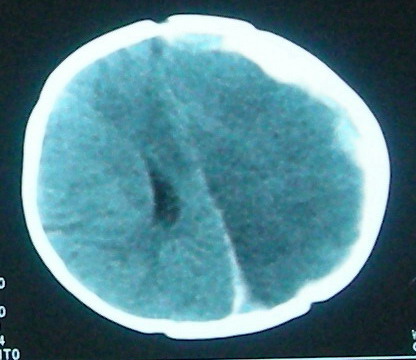

左侧大脑半球和右侧额叶大片低密度影,脑沟及外侧裂池消失,左侧脑室闭合,考虑脑梗塞伴有水肿。

左侧大脑半球和右侧额叶大片低密度影,脑沟及外侧裂池消失,左侧脑室闭塞,左侧蛛网膜下腔片絮状高密度影,结合病儿高热、脑膜刺激征(+),考虑:炎脑,脑水肿,左侧蛛网膜下腔出血。至于出血原因,应该为高热所致维生素c需要量增加,而补给不足所致维生素c缺乏,抑或是使用抗惊厥药影响维生素k代谢,使凝血发生障碍而出血。当然,一切都是猜测,需要临床进一步检查验证。